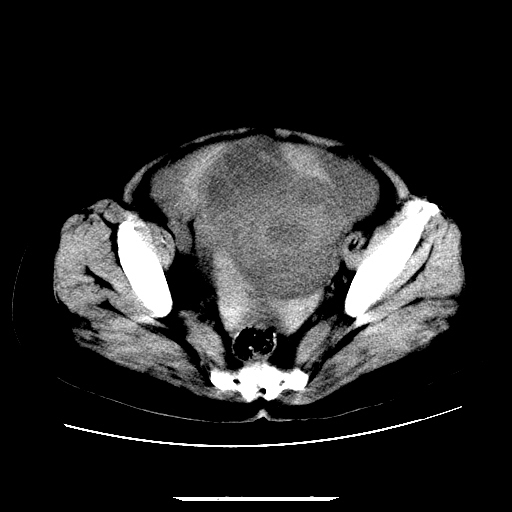

f,45y.怀孕4月晕倒,b超提示死胎,有手术结果,请展开讨论后明天告诉。

膈下-肠间隙内见气体密度影,子宫轮廓显示不清,宫腔-腹腔积液,首选考虑---子宫破裂出血。

1)宫腔妊娠。2)子宫破裂出血,腹腔及盆腔积血。

感谢同行们的高见。手术结果:子宫破裂出血。

我们的诊断是:腹、盆腔积液(考虑腹盆腔脏器破裂出血);宫腔妊娠。让人纳闷的是当时我们没有经验,现在回头看看分析:4月宫腔妊娠:1、洋膜囊不可能紧贴胎体这么小;2仔细看看子宫后壁肌层模糊不清;3腹、盆腔液体来源原因?4、45岁高龄妊娠有晕倒。由此可大胆诊断:宫腔妊娠子宫破裂出血。